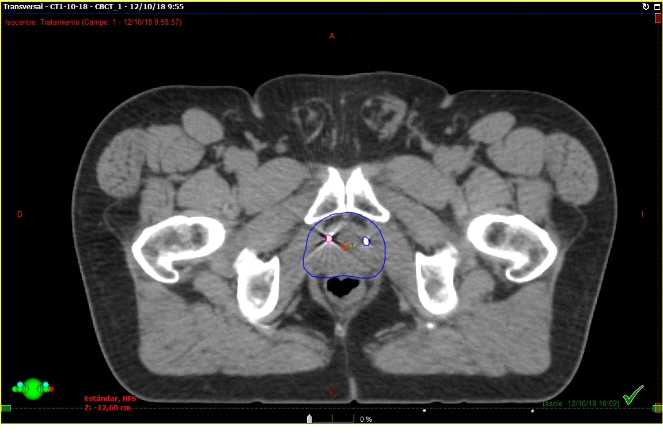

Fig. 3. Técnica de Radioterapia IGRT (Guiada por imágenes). Derecha: TAC de simulación con contornos: Rojo CTV: clinic target volume(próstata y vesículas seminales); Azul: PTV: patologic target volume); Amarillo: Vejiga (OAR); Rosado: Recto (OAR); Verde: Cadera derecha (OAR); Celeste: Cadera izquierda (OAR). Izquierda: Conbeam en máquina de tratamiento, en donde la imagen en el aceleradorse superpone con los contornos hecho en el TAC de simulación.